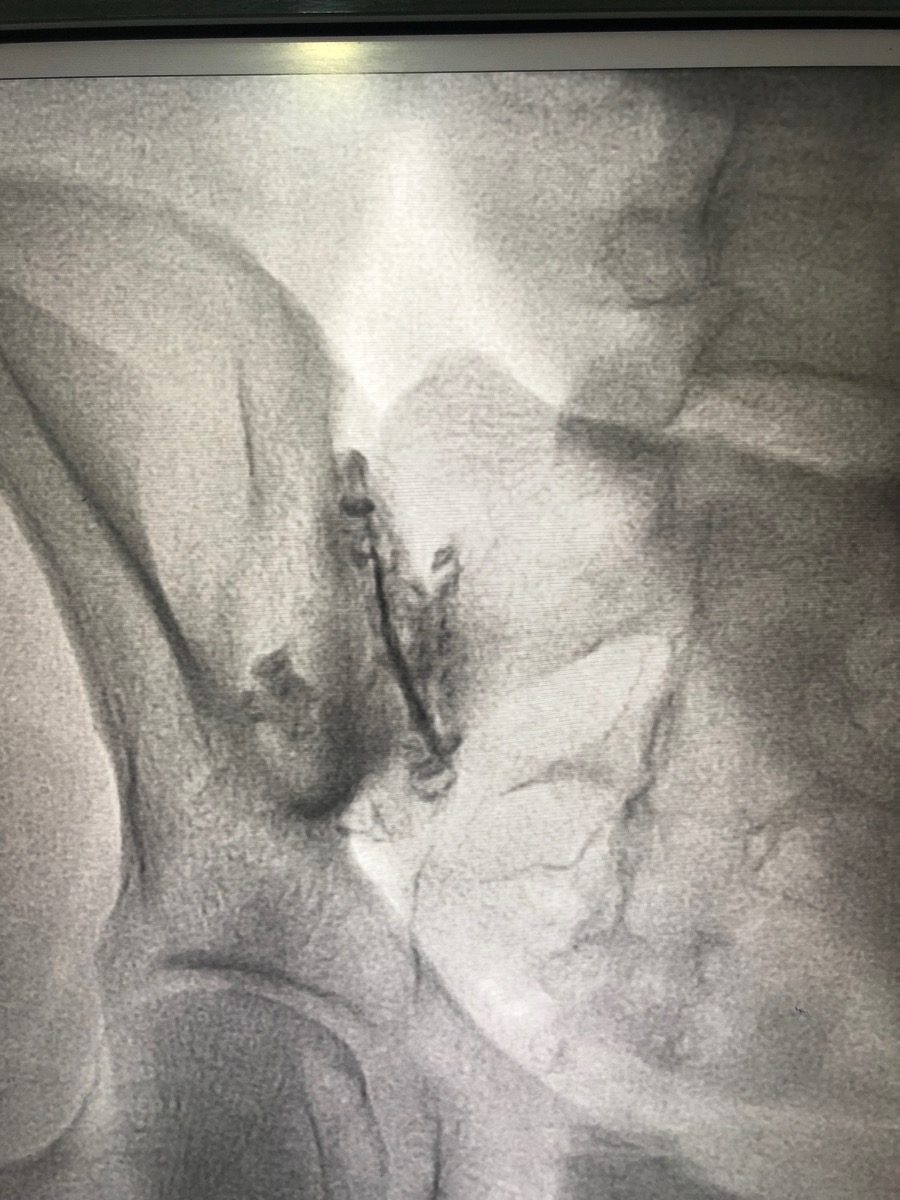

You lie face-down on the procedure table. The skin over your lower back and buttock area is cleaned and numbed. Under fluoroscopy (live X-ray) guidance, a thin needle is guided precisely into the SI joint. A small amount of contrast dye is injected to confirm the needle is inside the joint, then the steroid and anaesthetic are delivered. The procedure takes about 15–20 minutes.